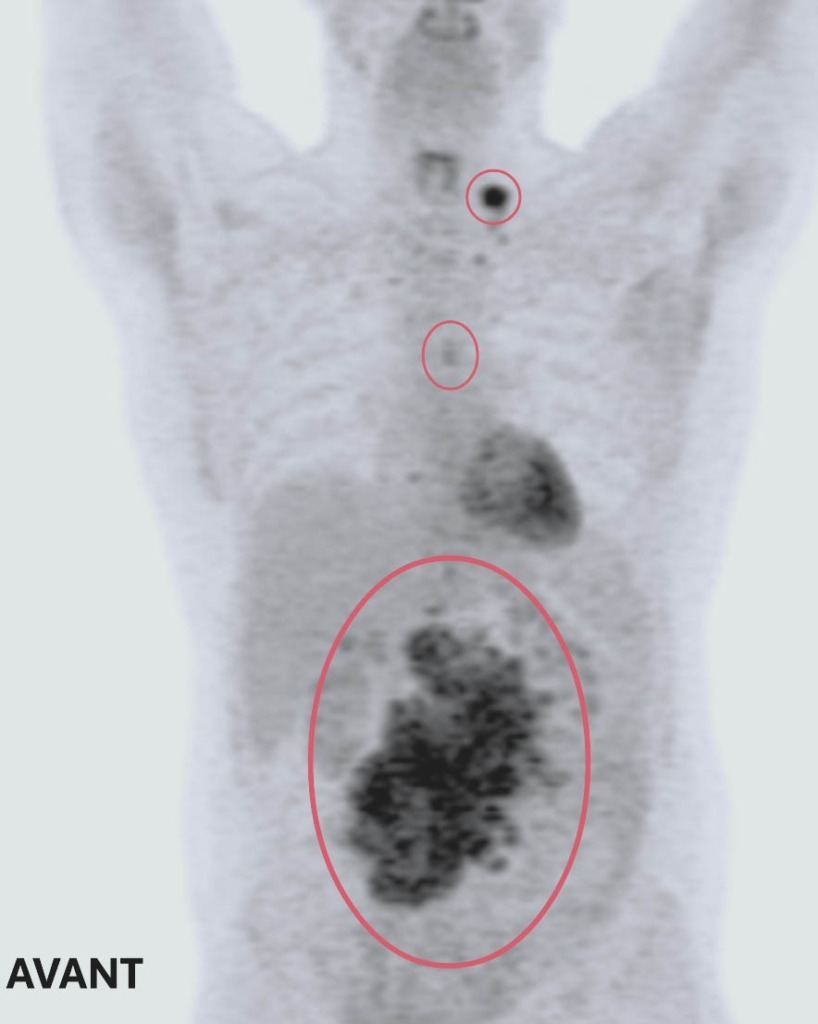

Une TEP révèle la présence de trois tumeurs. La plus grande et la plus préoccupante se trouve dans l’abdomen et mesure 14 cm x 14 cm x 9 cm – environ la taille et la forme d’une très grosse patate douce. Les deux autres sont près de son œsophage et de sa clavicule.

Clichés d’imagerie médicale avant et après ses traitements : deux des trois tumeurs de Ted ont complétement disparu. La troisième est maintenant de la taille d’un petit pois – Ted répond très bien au traitement suivi à L’Hôpital d’Ottawa.